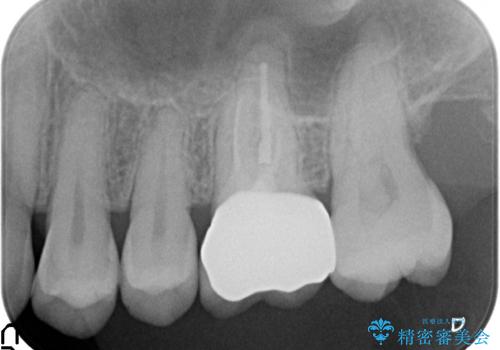

診査の結果左上6は失活していたため、根管治療を行った後にオールセラミッククラウンによる補綴を行いました。

- オールセラミッククラウン…¥100,000、仮歯…¥10,000、ファイバーコア…¥20,000、精密根管治療費別途費用は治療当時の料金となります

今回用いたオールセラミッククラウンは、ジルコニアフレームという白い素材の上にセラミックを盛っているため審美性が非常に高いのが特徴です。

またジルコニアは人工ダイヤモンドの材料にも使われているほど高い強度を持っており、そのためオールセラミッククラウンは審美性だけでなく、奥歯やブリッジの補綴も可能なクラウンです。